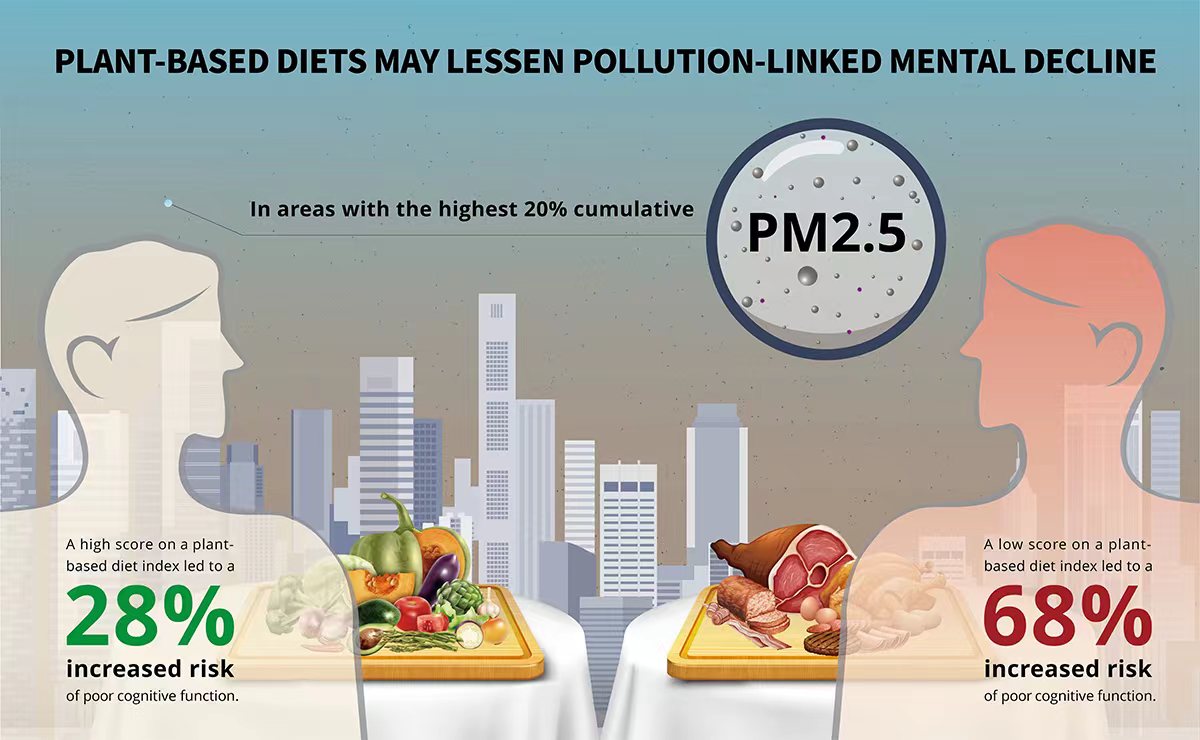

Pollution can worsen cognitive decline – but plant-based diets may help

Research is increasingly showing an association between air pollution and cognitive decline. So, how can we reduce the risks of ubiquitous dirty air on our brain? A new study has found that a plant-based diet may mitigate the detrimental impacts of fine particulate pollution (PM2.5) on cognitive ...